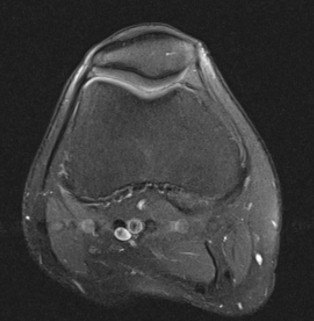

3.MRI(以膝关节为例)

由于MRI和CT一样也 是三维成像,包括矢状面,冠状面和横断面三个层面的扫描。一张MRI片子也是包括医院、姓名、性别、年龄、检查日期、侧别、扫描序列等信息的。不同的示MRI在片子上是信号的高低(CT时密度的高低),也就是说有T1和T2序列(T2序列表现为关节积液是高信号-发白;T1序列表现为关节积液为低信号—发黑或发灰)。因此MRI上不仅有矢状面、横断面和冠状面,还有T1序列和T2序列。

一般来说T2序列更能反应损伤情况,所以平时观察T2序列的图像要更仔细。T1序列主要观察解剖结构,有些医院一般不常规做。

T2序列横断面